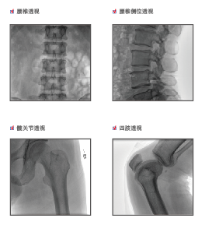

普愛醫(yī)療是專業(yè)從事平板小C生產(chǎn)、研發(fā)、售后為一體的廠家,目前我們應(yīng)用在國內(nèi)很多醫(yī)院的一款PLX118F平板C形臂,它是一臺集光、機、圖像處理技術(shù)為一體的帶數(shù)字減影血管造影功能(DSA)的可移動式X光機,該設(shè)備占地面積小、圖像清晰、定位精準、輻射劑量小,是疼痛科醫(yī)生的可靠眼睛,對于疼痛介入手術(shù)的精準化治療、滿足患者對慢性疼痛治療需求提供了有利條件。